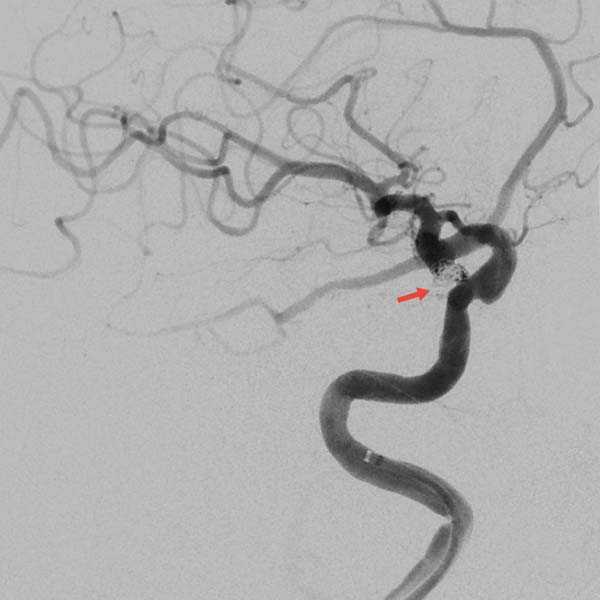

▲右颈内动脉3D-DSA显示两个动脉瘤

后交通动脉瘤不规则

瘤颈处发出胚胎型大脑后动脉

瘤顶端可见子瘤(红箭头)

▲术后即刻造影见动脉瘤近致密栓塞

载瘤动脉及胚胎型大脑后动脉通畅